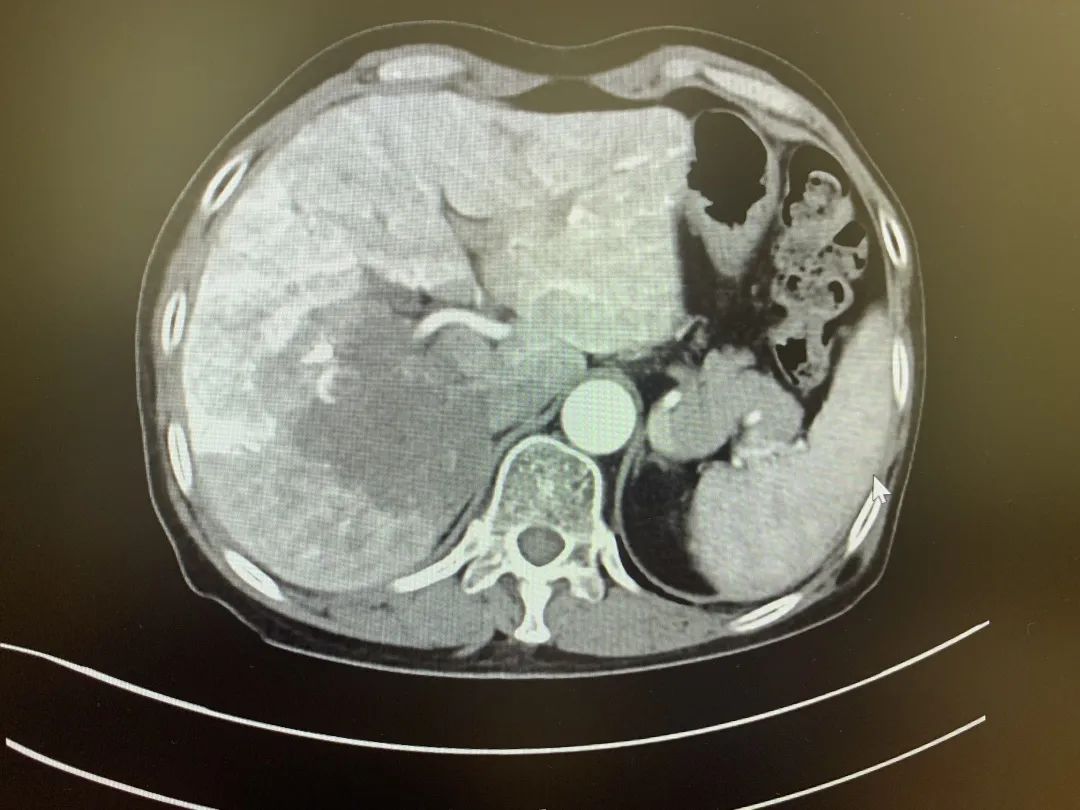

术前CT

患者桂女士,63岁,5月11日出现无明显诱因的中上腹间歇性隐痛,伴恶心呕吐、反酸、腹泻等症状,随即来到我院消化疾病中心门诊就诊,门诊以“腹痛待查”收入消化疾病中心肝胆外科进行进一步辅助检查,检查结果显示,肝右叶101*93mm的占位性病变,考虑肝癌可能。